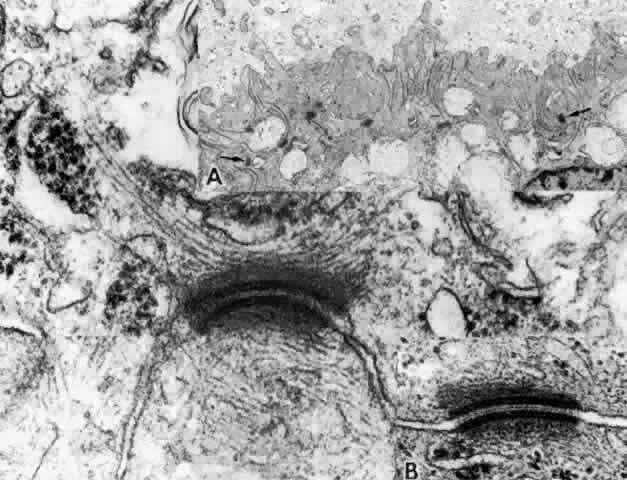

There are a large number of intercellular junctions between the ciliary epithelial cells, each giving important data about the specific functions of these cells (see Fig. 11). Toward the base of the NPE cells their lateral sides are joined by desmosomes (see Fig. 15). At their apical ends they are connected by typical tight junctional complexes consisting of a zonula occludens and zonula adherens (Fig. 19). These tight junctions represent the primary blood-aqueous barrier in the ciliary body. When large tracer molecules such as horseradish peroxidase are injected intravenously into primates,20,21 the tracer has an easy passage through the fenestrated capillaries of the ciliary processes, but does not pass beyond the apices of the NPE cells (see Fig. 19).

Fig. 19. Evidence of tight junctional complexes in the anterior ciliary epithelium of Macaca mulatta. The pigmented epithelial cells (PC) are outlined by a thin black line that is the reaction product of horeseradish peroxidase, a tracer substance injected intravenously in vivo. The tracer has entered the intercellular spaces of the nonpigmented epithelium (NPC) but is held up by occluding junctions (arrowheads), preventing further progress into the posterior chamber. (X 8450; Courtesy of Dr. Guiseppina Raviola)

The zonula occludens is the primary component of the blood-aqueous barrier “tight junction.” It appears as a focal area at which the bilayered plasmalemmal membranes of each cell surface are tightly joined (Fig. 20). Zonular adherens junctions occur adjacent to occludens junctions on the basal side. They show a 12- to 15-nm space between the adjoining cells, with filamentous matrix material clinging to the cell membranes on either side. By the freeze-fracture technique, the zonula occludens consists of branching anastomosing strands on the cytoplasmic side of the plasmalemmal membrane (P-face) and matching grooves on the external side (E-face), giving a quilted effect (Fig. 21). The variation in number of strands seen from area to area in the ciliary zonula occludens region23 is consistent with physiologic evidence that the NPE is leaky to ions and small molecules, rather than being an absolute barrier like that between the endothelial cells of the retinal vessels. Ohnishi and Kuwabara24 found the tight junctions of the anterior pars plicata had the fewest strands, explaining why this region is so sensitive to leakage after paracentesis in several species.

Fig. 20. Apical junction of two nonpigmented epithelial cells (NPE) showing focal zonula occludens (ZO) junctions (arrows), an adjacent zonula adherens (ZA), and desmosome (D), puncta adherentes (PA), and gap (G) junctions. PE, pigmented epithelium. (X 58,700)